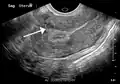

-

A very large (9 cm) fibroid of the uterus which is causing pelvic congestion syndrome as seen on CT -

A very large (9 cm) fibroid of the uterus which is causing pelvic congestion syndrome as seen on ultrasound -